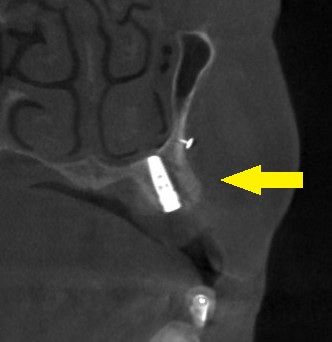

本日、2本のインプラント埋入と骨造成術を施行しました。

下の写真3段目が手術後のCTです。